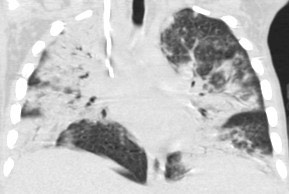

1946. У пациента 10 лет с нейтропенией при компьютерной томографии в легких определяются массивные зоны уплотнения легочной ткани сливного характера с преимущественным перибронхиальным расположением, корни легких на фоне инфильтратов не дифференцируются, рентгенологическая картина соответствует